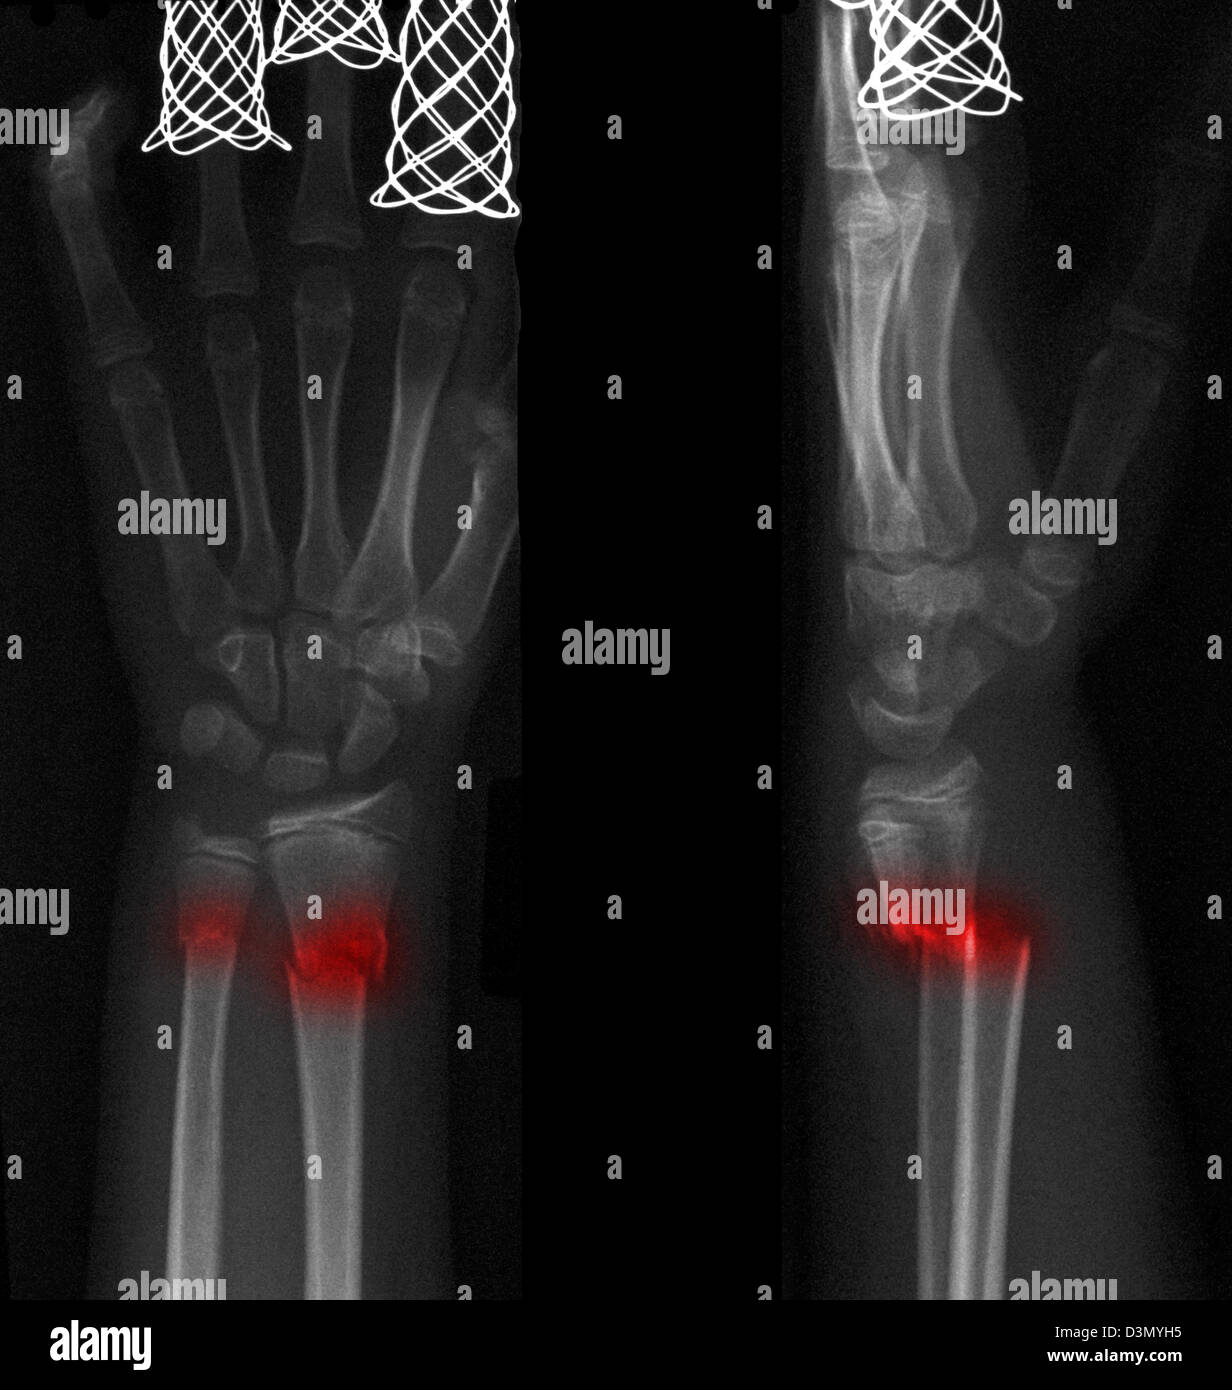

x ray of right hand and wrist

Posts: x ray of right hand and wrist